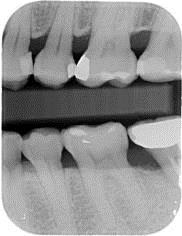

術後一年之全口X光片, #37近心側可見明顯骨充填與放射線密度增加。 牙周再生手術完成一年後追蹤,全口牙齦發炎狀況改善,牙周組織呈現健康狀況。#37金屬燒附陶瓷牙冠製作完成。